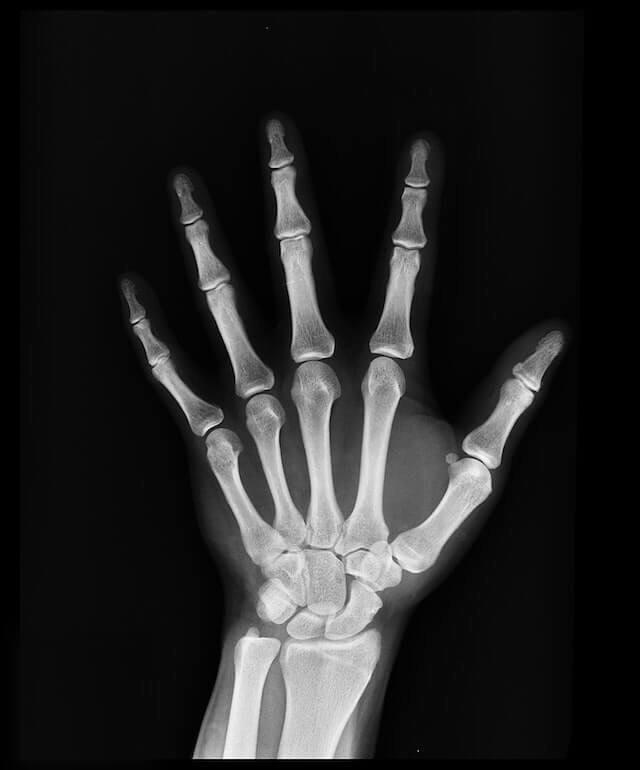

Looking after your bone health is important because by keeping your bones strong, you reduce the risk of aches, pains and fractures.

Strong bones also mean less chance of osteoporosis or brittle bones. This is when the bones weaken over a long period of time, becoming less dense, more fragile and more vulnerable to fractures.